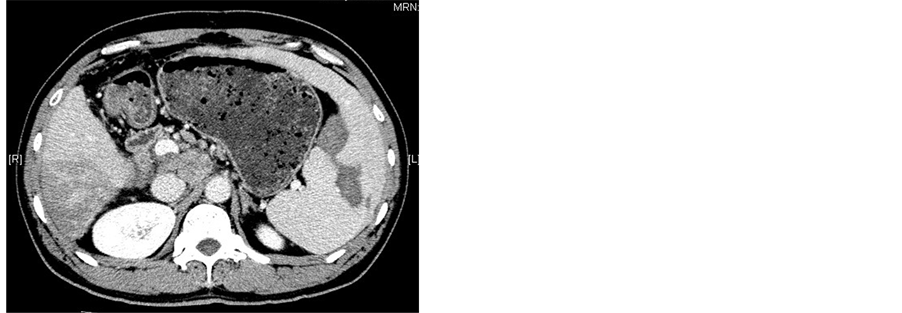

All patients underwent abdominal CT scanning (GE Medical Systems) 1 wk before procedure and 2 wk after procedure to evaluate the necrosis of the spleen (Figure 2). After treatment with MWA combineed with TACE, all patients remained in hospital with their adverse effects or complications observed and were then followed up at outpatient clinic. Peripheral blood cell parameters including white blood cells (WBC), platelets (PLT) and red blood cells (RBC) were obtained 1 wk before procedure and 1 wk, 2 wk, 1 mo, 2 mo, 3 mo after procedure.

Figure 2. (a)-(c) Contrast-enhanced CT scans of the spleen before splenic MWA; (d)-(f) Two weeks after MWA. Contrast-enhanced CT scans showed unenhanced low attenuation ablated area in inferior part of spleen. The ablation ratio was about 20%.